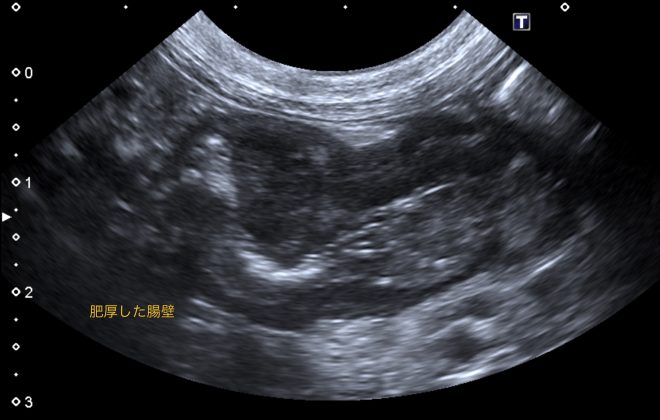

腹部超音波検査で、回盲部(小腸と大腸の境目)の腸壁の肥厚を認め、細胞診で腫瘍性疾患を疑う結果でしたので、CT検査で転移の有無を確認し、回盲部切除を行いました。

病変の超音波画像

病変の超音波画像